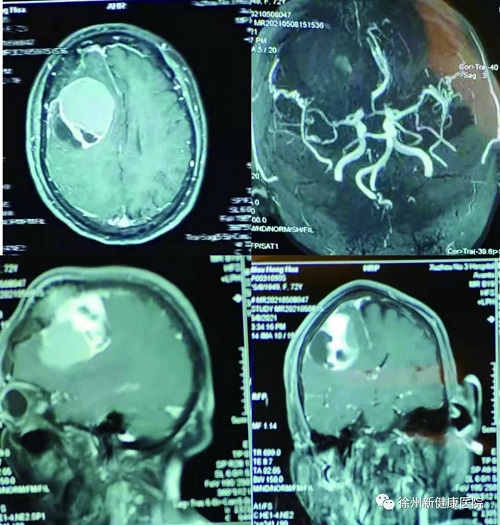

近日,徐州新健康医院神经外科梁元博士团队成功为一名患者切除8cm、拳头大小的罕见巨大脑肿瘤。术后患者各项指标正常,目前已康复出院。

梁元博士接诊后,对许大娘进行了细致的检查,右侧额部可触及皮下肿块,肿块比较硬,大小约为6cm×8cm。同时,许大娘的脑部肿瘤导致大脑电生理功能的异常,引起大脑局部皮层异常放电,右侧面部出现抽搐,右眼睑不自主跳动,舌头也向右偏。诊断为颅内占位性病变,必须立即实施手术治疗。

在积极术前准备后,手术如期开始。梁元博士对患者行脑血肿清除术,患者随时出现的种种风险无不考验着医疗团队。术中,可见颅骨破坏面积约3cm×5cm、骨窗扩大约8cm×10cm、及硬膜下发蓝的肿瘤。这个区域的肿瘤手术极易导致偏瘫,复杂的情况增大了手术难度系数,骑跨的静脉让手术难上加难。梁元博士打开硬脑膜,用瘤内吸引器吸除脑瘤,逐渐打薄肿瘤,但后面的肿瘤极硬韧,术中耐心细致的分离中央前回与肿瘤间隙,保护中央沟静脉及皮层回流静脉,最终完整切除肿瘤,梁元博士团队凭借丰富的经验及成熟的手术技能,成功解决术中遇到的种种难题,经过两小时精细手术,将脑肿瘤及部分水肿失活组织全部切除。

术前术后对比